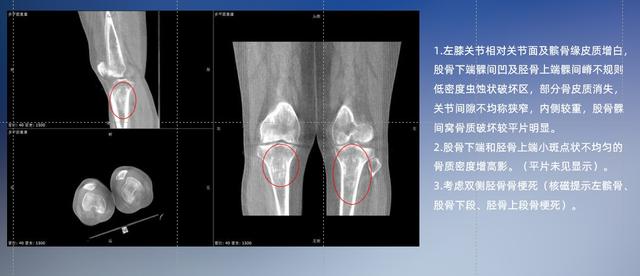

以膝關節疾病檢查為例,膝關節在解剖學意義上是一種較為復雜的最大關節,由脛骨上端、股骨下端及髕骨組成。在股骨與脛骨的關節面之間存在兩塊半月板,分別處于內側、外側。膝關節的運動主要為伸、屈,在半屈位時可進行小幅度的旋外、旋內運動。隨著現代人們體育生活以及肥胖的增加,膝關節疾病出現高發趨勢,特別是關節磨損、膝關節炎與骨關節炎等關節退行性改變,長時間的內翻負荷會造成內側關節軟骨、骨性關節面的磨損。目前針對此類疾病的檢查主要為平片下的負重位檢查、CT檢查以及MRI檢查,相較于非負重位檢查,負重位檢查能更加真實反映膝關節結構中脛骨、股骨、髕骨實際對位關系和關節面的形態特征及關節間隙大小,對膝關節骨關節病診斷準確率高。

普通平片掃描與WR-3D掃描前后診斷結果對比

與此同時,數字化X線攝影技術相較于CT和MRI來說,能快速獲取真實、直觀、滿足臨床需要的影像。DR的圖像具有圖像層次豐富、空間分辨力高、影像邊緣銳利清晰、密度分辨力高級細微結構表現出色等特點,針對膝關節解剖結構數字化X線攝影技術應用價值很高,尤其是是對骨小梁與骨皮質的顯示非常清楚。在負重位狀態下,數字化X線三維攝影掃描與重建,能夠更好的呈現受檢者關節受力改變的狀態。安健科技創新的WR-3D動態三維數字化X線攝影技術,通過數字化X線攝影完成三維掃描并重建三維影像信息,包括MPR多平面重建、MIP重建以及VR繪制。掃描時間短,劑量相較于CT設備大幅縮減,同時成本更低,在臨床診斷以及醫療方案制定中具有極大的價值意義。相較于普通平片下的負重位掃描,負重位動態三維掃描攝影技術能夠避免二維狀態下的組織結構重疊、密度分辨率不足、組織解剖結構難以分辨等問題,WR-3D支持多角度的動態三維攝影觀察,能全面的呈現被檢查部位在多個角度下三維影像信息,極大的減少了二維負重位檢查的漏診率。